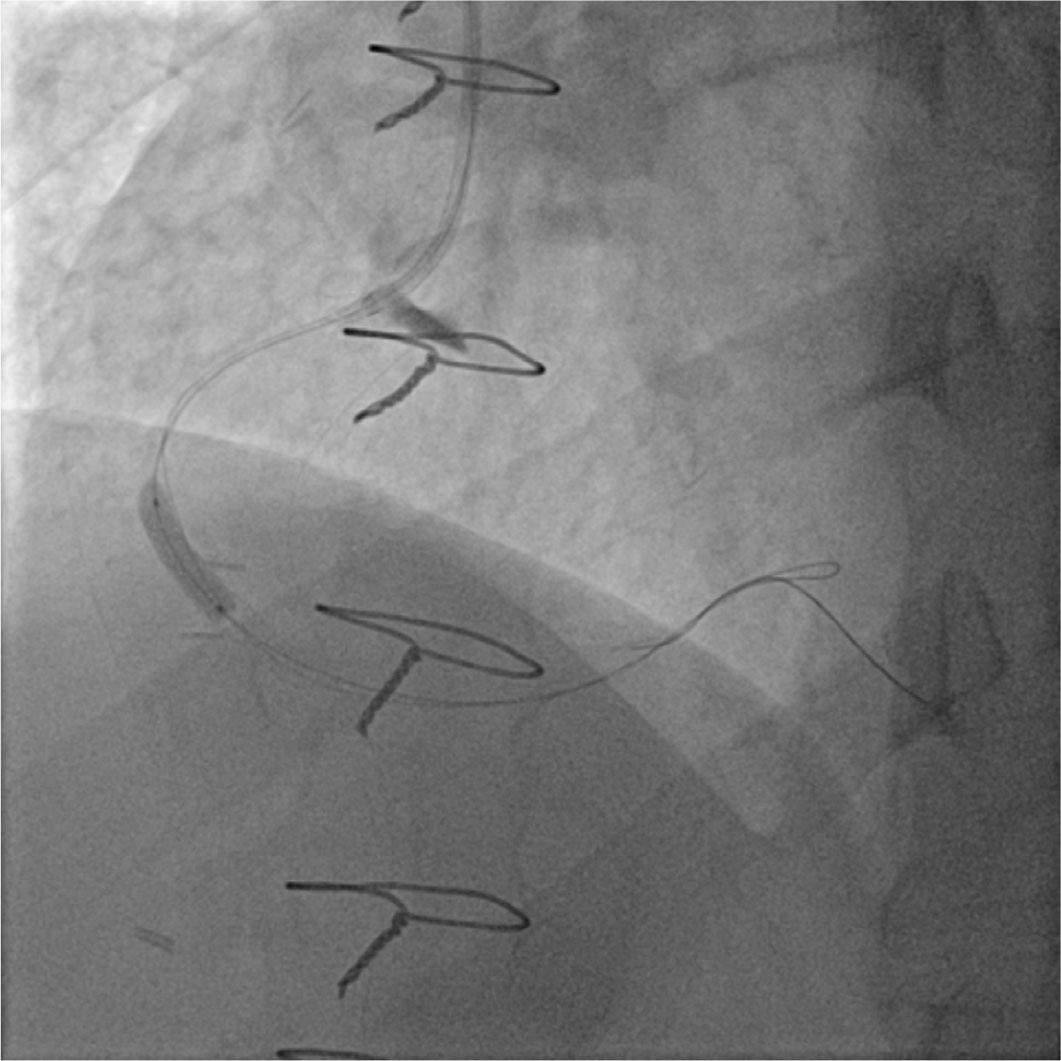

Because the guidewire appeared to be in the false lumen, it was withdrawn and replaced with a 0.014” CHOICE PT Floppy guidewire (Boston Scientific), which was successfully used to cross the lesion. The proximal dissection flap was sealed using a Resolute Integrity drug eluting stent (DES) deployed into the RCA ostium at 16 atm. Afterwards, a buddy wire was used to aid in the delivery of two short Prokinetic Energy 3.5/15 mm (BIOTRONIK) and 3.5/13 mm (BIOTRONIK) bare metal stents (BMS) placed in the distal segment at 14 and 16 atm, respectively. Lastly, a 4.0/38 mm Resolute Integrity stent (Medtronic) was used to cover the culprit lesion and seal off the dissection in the mid-proximal part of the RCA (Figure 3), with a good final angiographic result and restoration of Thrombolysis in Myocardial Infarction (TIMI) grade 3 flow (Figure 4). Final angiography and aortography with pigtail catheter showed complete sealing of the dissection flap. Also, a CT scan conducted two days later showed patent RCA stents with no evidence of dissection (Figure 5). The patient remained asymptomatic on guideline-recommended medication after myocardial infarction and was discharged from the hospital five days later.

Stenting the origin of the dissection.

Deployment of the third stent through “buddy wire” technique.